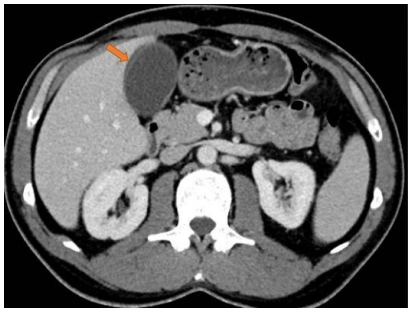

Observe o exame a seguir para responder as questões 39 e 40.

A seta em destaque aponta para

O método de imagem utilizado evidencia

Na avaliação de um nódulo hepático, um dos exames realizados é a tomografia computadorizada do abdome. A sequência das fases de aquisição das imagens deve ser, respectivamente,